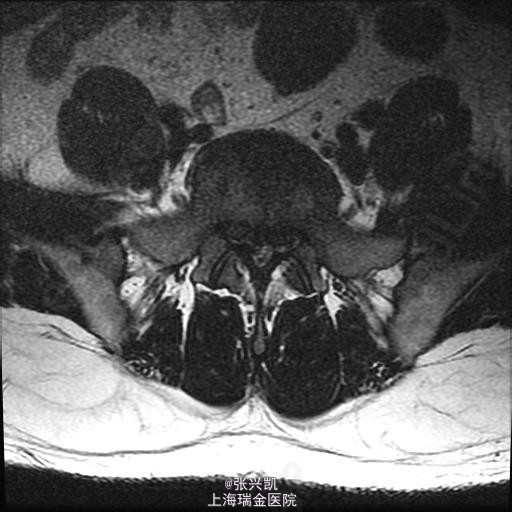

查体:脊柱无侧弯畸形,双上肢感觉活动良好,双侧股四头肌肌力正常,跟、膝腱反射(+),右腿直腿抬高试验45°,左侧70°,右侧足踝外侧麻木感 辅助检查:腰椎MR示:L4-5,L5-S1,椎间盘突出,相应节段伴狭窄,腰椎退行性改变,L5,S1相邻终板变性。

诊断: 1、腰椎椎间盘突出(L4-5,L5-S1) 2、腰椎椎管狭窄(L4-5,L5-S1) 处理: 经后路行L4-5,L5-S1椎管减压,椎间盘摘除,L4-5,L5-S1融合内固定术